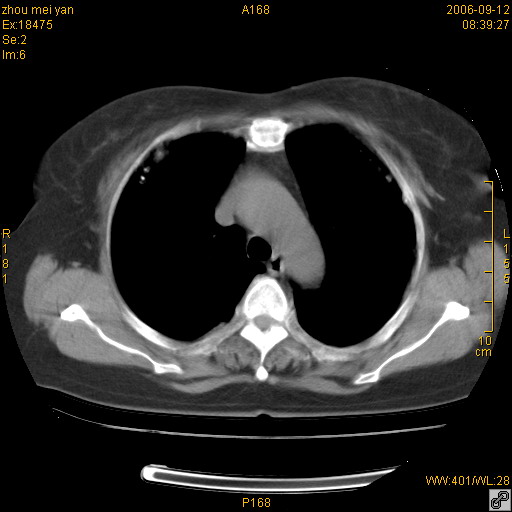

患者、女、55岁。因心率失常住院检查ct发现胸部多发结节。腹部b超肝、胆、胰、脾、肾、子宫附件未见异常。无结核病史,无粉尘接触史。请大家来会诊。谢谢!

病变位于胸膜,多发结节,边界清楚,内见小结节状钙化。其它未见异常。

多发胸膜表面的结节,基本对称,部分有钙化。首先考虑类风湿性胸膜结节,次则考虑结核性胸膜炎后遗之胸膜结节状增厚、钙化。

双侧胸膜多发结节,形态不规则,边缘较清楚,每一个结节中心似乎都有钙化点的特征,与胸膜广基相切。临床无结核病史,无粉尘接触史。

影像表现十分有特点:双侧肋胸膜及膈胸膜广泛散在分布大小在2至6mm左右,较大病灶中心可见钙化。

双侧肋胸膜及膈胸膜广泛散在分布大小不等结节影,较大病灶中心可见钙化。